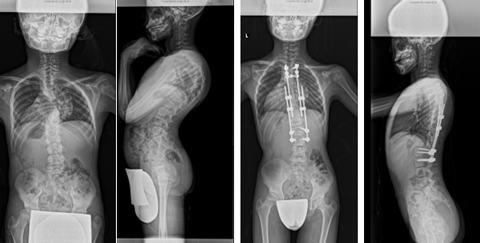

腰椎固定術後後弯に対する椎体骨切り術を併用した後方矯正固定術

前方後方矯正固定術

せぼねが大きく変形している場合や再手術の際に前方手術と後方手術を両方行って、せぼねの矯正と固定を行います。

1日で両方の手術を行う場合と2日間に分けて手術を行う場合があります。大人の患者様では3週間程度で場合によってはリハビリテーション病院へ転院をしていただき、さらにリハビリテーションを行います。